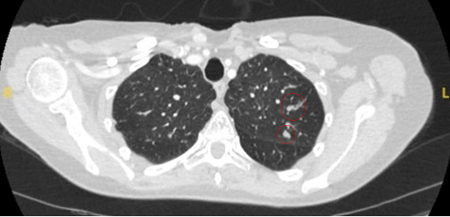

The most likely cause of benign solitary pulmonary nodules will depend on the local epidemiology of disease. For example, at a US academic centre, 23% of patients undergoing resection of a suspicious nodule had benign pathology, with granulomatous disease, such as tuberculosis and fungal infections (e.g., histoplasmosis, coccidioidomycosis, aspergillosis), identified as the most common cause.[10] Non-infectious granulomas are usually due to granulomatosis with polyangiitis (formerly known as Wegener's granulomatosis), sarcoidosis, or rheumatoid arthritis.[Figure caption and citation for the preceding image starts]: Computed tomography (CT) showing a right upper lobe posterior cavitating nodule, with biopsy confirming granulomatosis with polyangiitisFrom the collection of Dr George Tsaknis, MD, PhD, FRCP(London), MRQA, MAcadMEd, PGCert; used with permission [Citation ends].